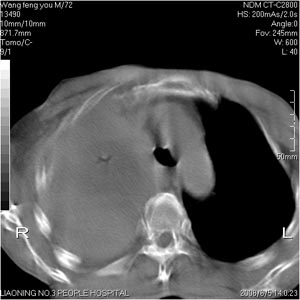

患者:男 72岁 右肩痛半年,近日来咳血,就诊.

考虑:右肺上叶中心型肺癌伴肺不张、肋骨转移、肩胛骨转移、右侧胸腔积液。

考虑 右肺上叶中心型肺癌伴肺不张,多发肋骨转移,胸骨上窝转移;右侧胸腔积液。

右肺上叶中心型肺癌伴肺不张、肋骨、肩胛骨、锁骨上淋巴结、右侧胸膜多发转移。